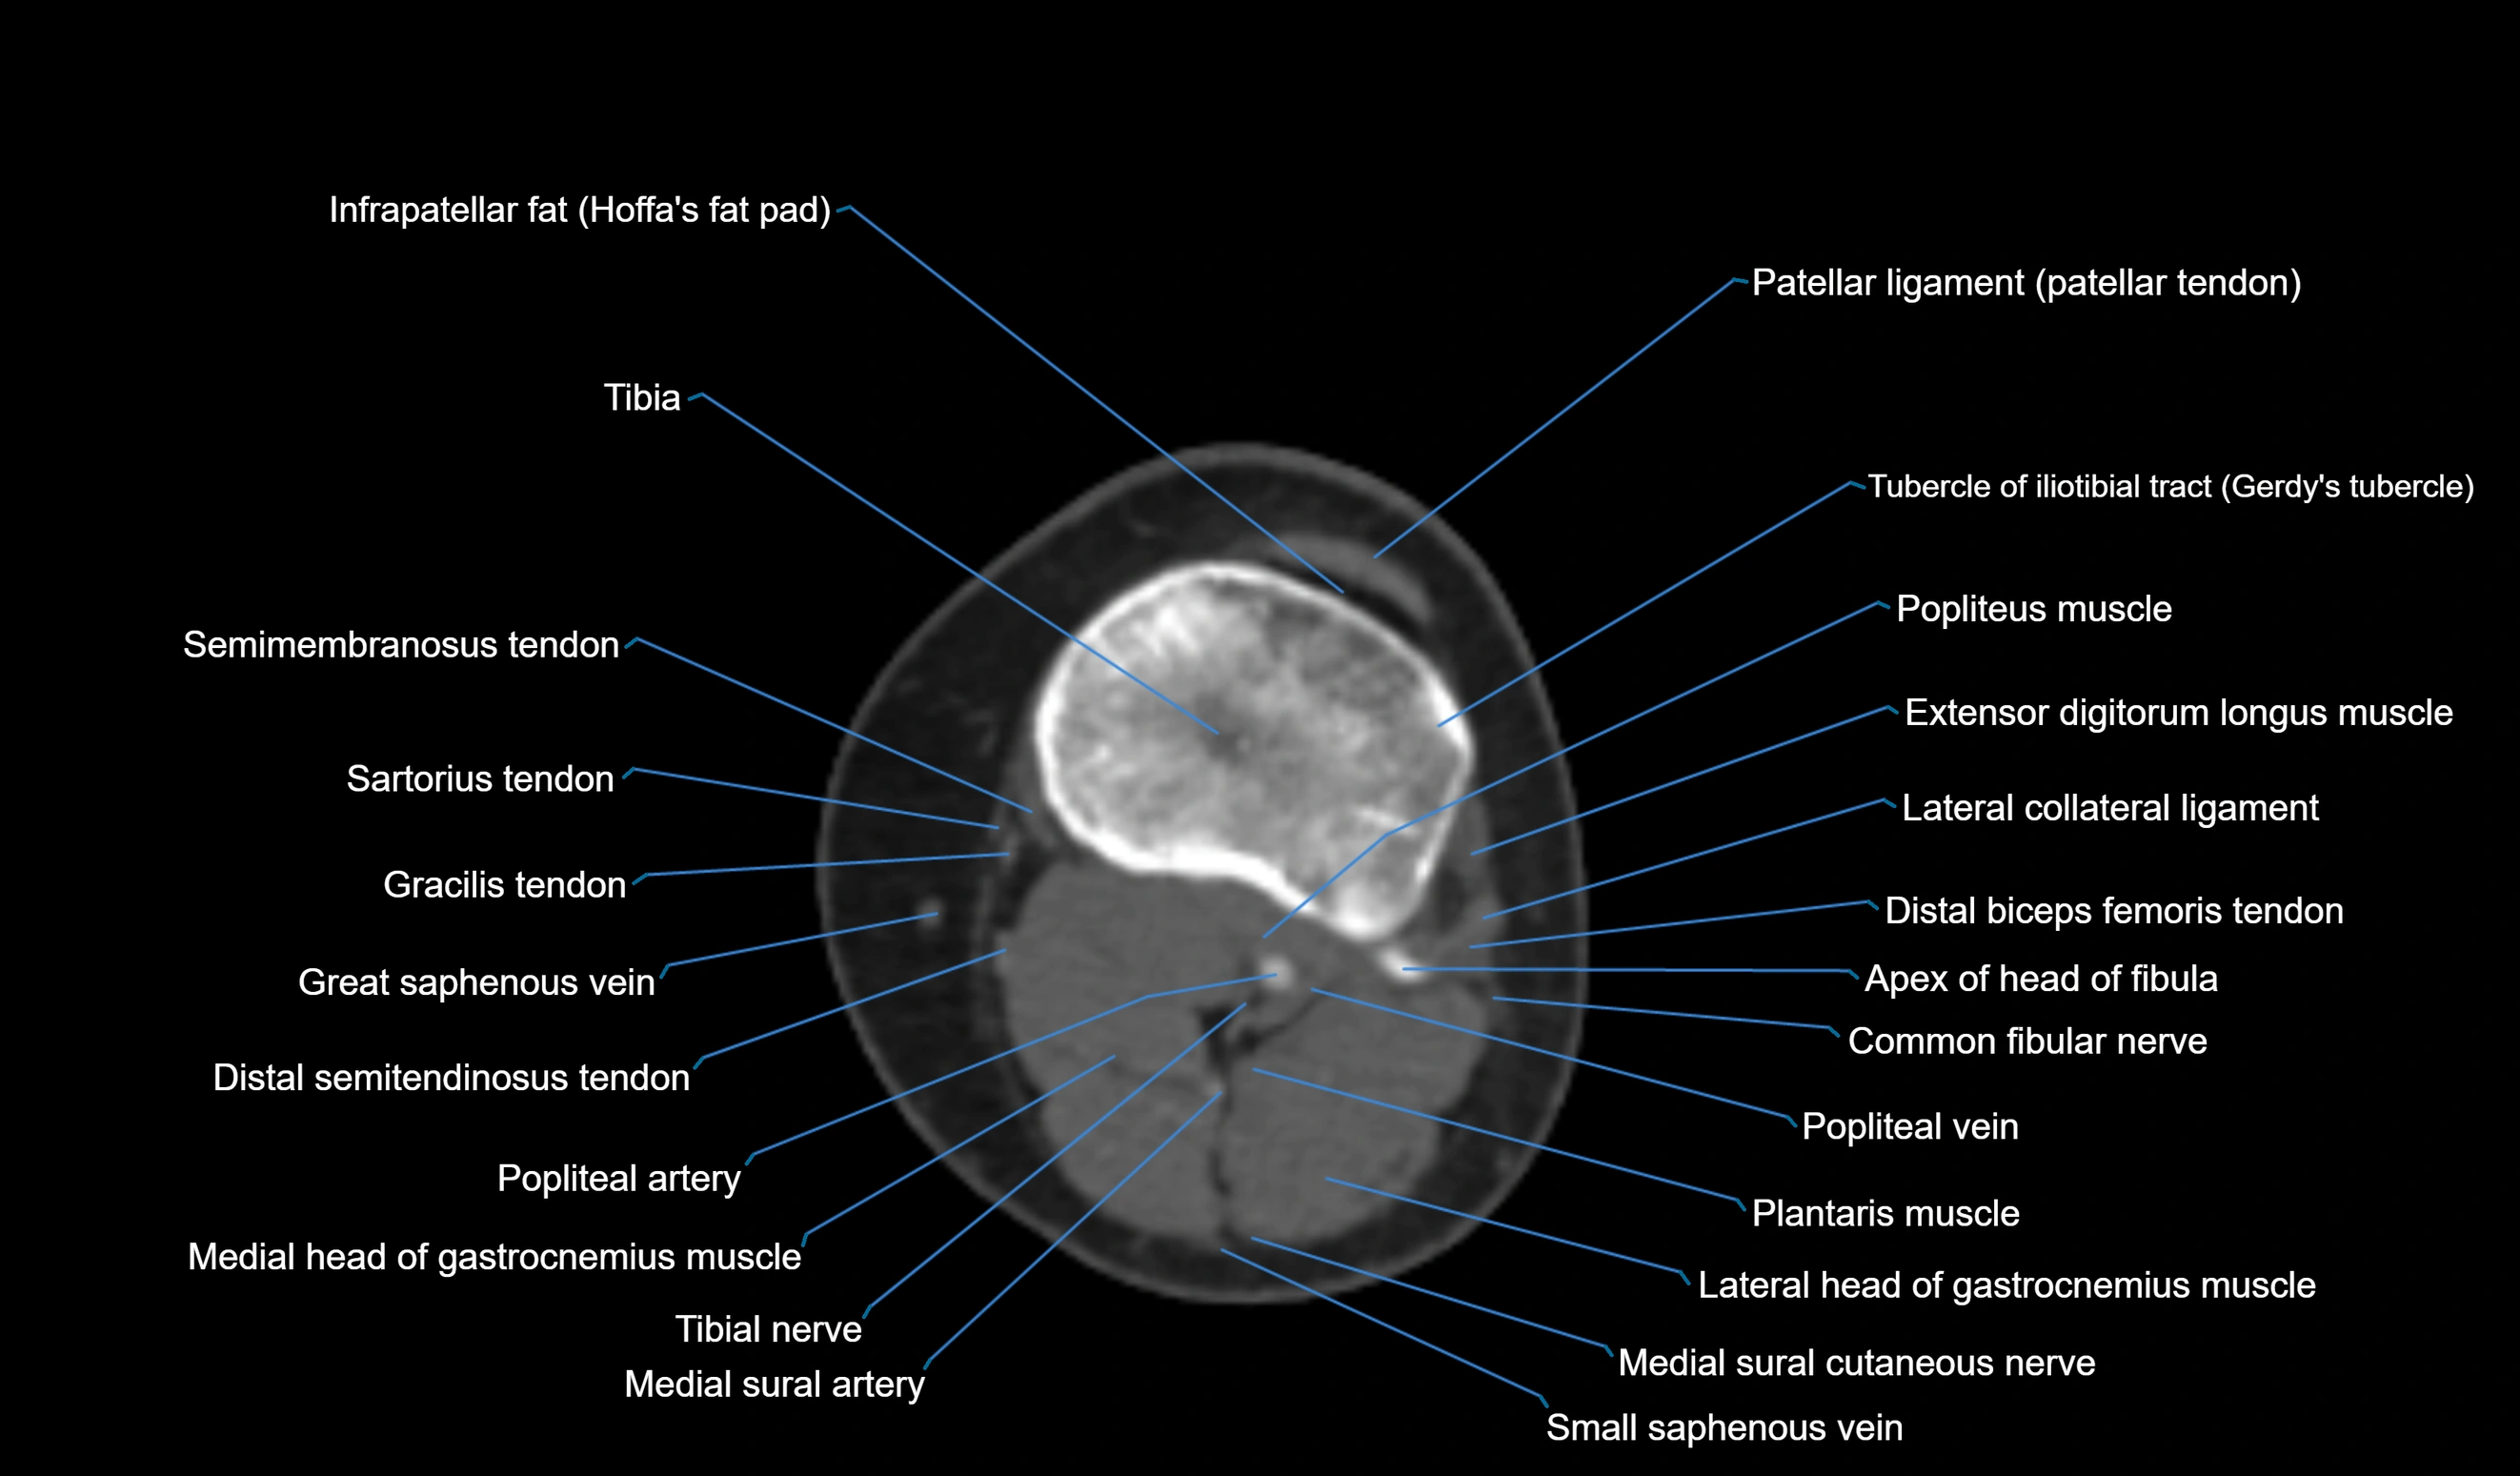

- Gracilis tendon (Distal)

- Lateral collateral ligament

- Lateral head of gastrocnemius muscle

- Medial head of gastrocnemius muscle

- Patellar tendon (patellar ligament)

- Popliteal artery

- Popliteal vein

- Popliteus muscle

- Sartorius tendon (Distal)

- Tibia

- Tubercle of iliotibial tract